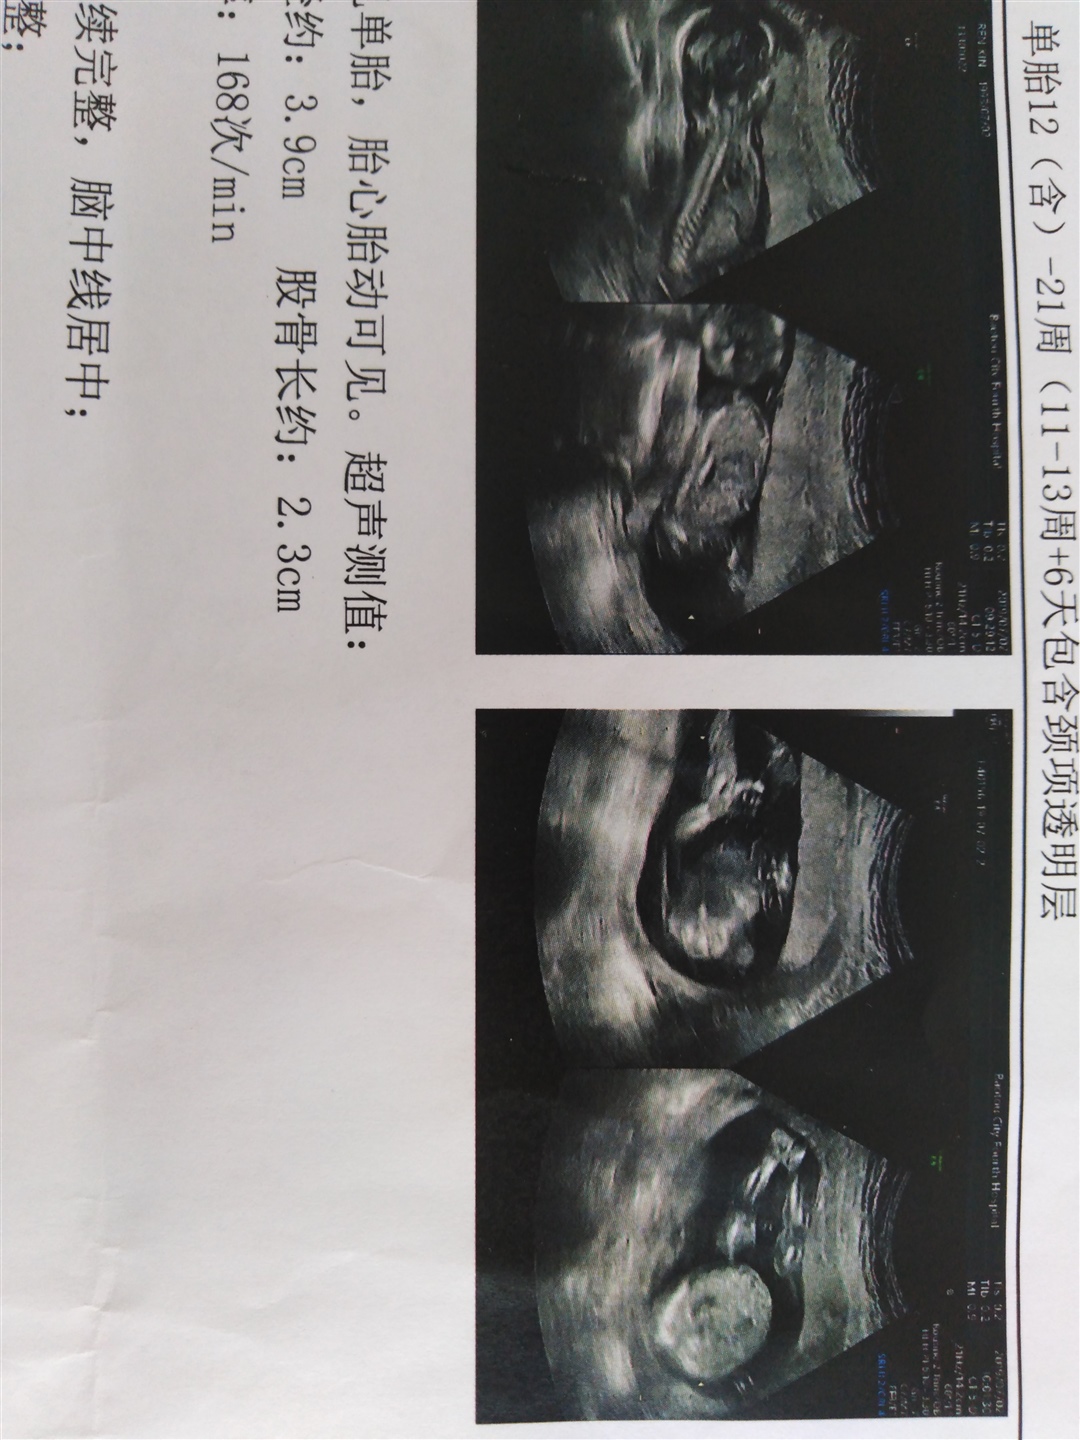

浪味仙.:最后一张要是腿的话 这孩子两腿中间有个小点点 点开 放大看就看见了

最后一张要是腿的话应该是男孩子吧